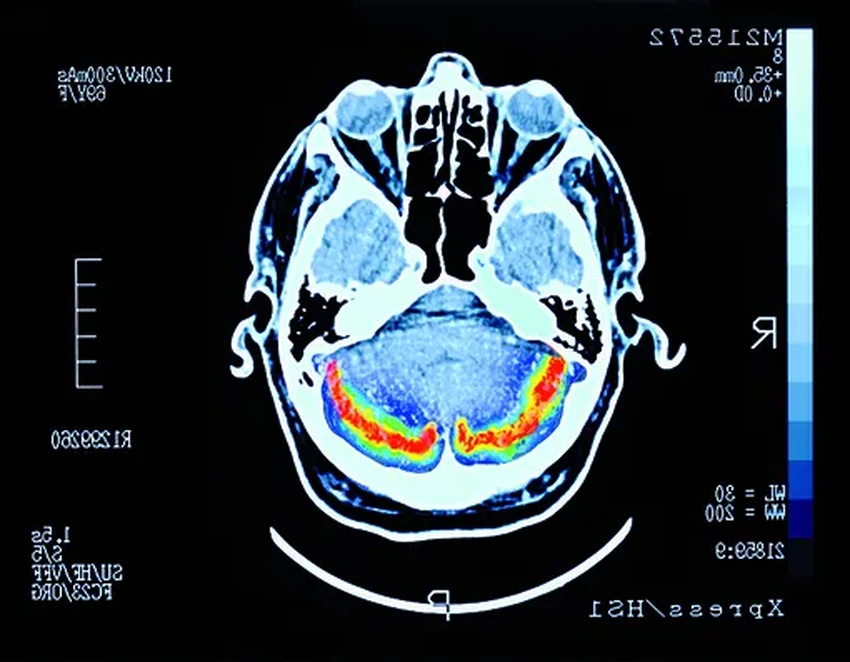

Компания «Тест здоровья» совершила нечто, за что ей скажут спасибо миллионы семей. Они разработали методику, способную выявлять болезнь Альцгеймера на самой ранней, доклинической стадии — по анализу белка в крови.

Сейчас эту болезнь диагностируют поздно, когда мозг уже серьёзно повреждён. Лечение лишь немного замедляет процесс. Разработка российских учёных может кардинально изменить правила игры.

Компания — резидент «Сколково». Их технология позволяет обнаруживать в плазме крови специфичные белковые биомаркеры, сигнализирующие о начале болезни. Четыре года исследований требовали проверки на реальных пациентах. Идеальной площадкой стала Психиатрическая больница №1 им. Алексеева.

В ближайший год методику планируют финализировать, получить регистрационное удостоверение и передать в медицину. А больница, кстати, уже не хочет расставаться с разработкой — врачи продолжают её использовать, расширяя выборку пациентов.